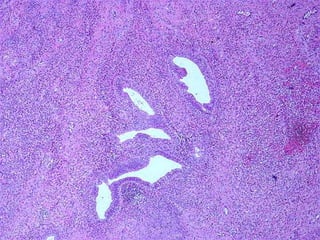

SEROUS, BENIGN

MUCINOUS, BENIGN